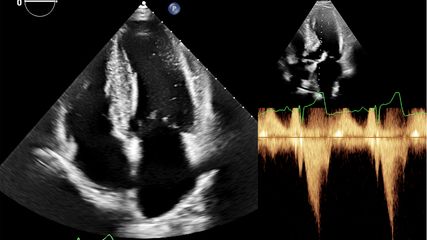

U. Attenberger: Für die Untersuchung von kardiologischen Patienten steht eine Reihe bildgebender Verfahren zur Verfügung, vom Thoraxröntgen über den Herzultraschall bis hin zu Computertomografie und Magnetresonanztomografie. So können wir in der MRT sehr gut die Herzfunktion messen, Myokarditiden darstellen und aus den Bildern auch prädiktive Marker ableiten wie bspw. die Regenerationswahrscheinlichkeit einer Läsion. Die Forschung geht in Richtung bildbasierter Biomarker.

U. Attenberger: Das Herz ist für die Bildgebung kein einfaches Organ, weil es sich permanent bewegt –nicht nur für die MRT-Bilddatenakquisition macht es das schwerer. Dass KI ein brandaktuelles Thema ist, sieht man gut an der großen Zahl der Resultate zu diesem Themenkomplex in einer PubMed-Recherche. Das Bonner kardiale Bildgebungsteam forscht zum Beispiel unter anderem daran, mathematisch zu berechnen, welche Position der Herzmuskel zu welchem Zeitpunkt im Verlauf des Herzzyklus hat. Sinn der Sache ist, Artefakte aus der Bildgebung herauszurechnen und die KI auf breiterer Basis in die bildgebende Diagnostik einzuführen.